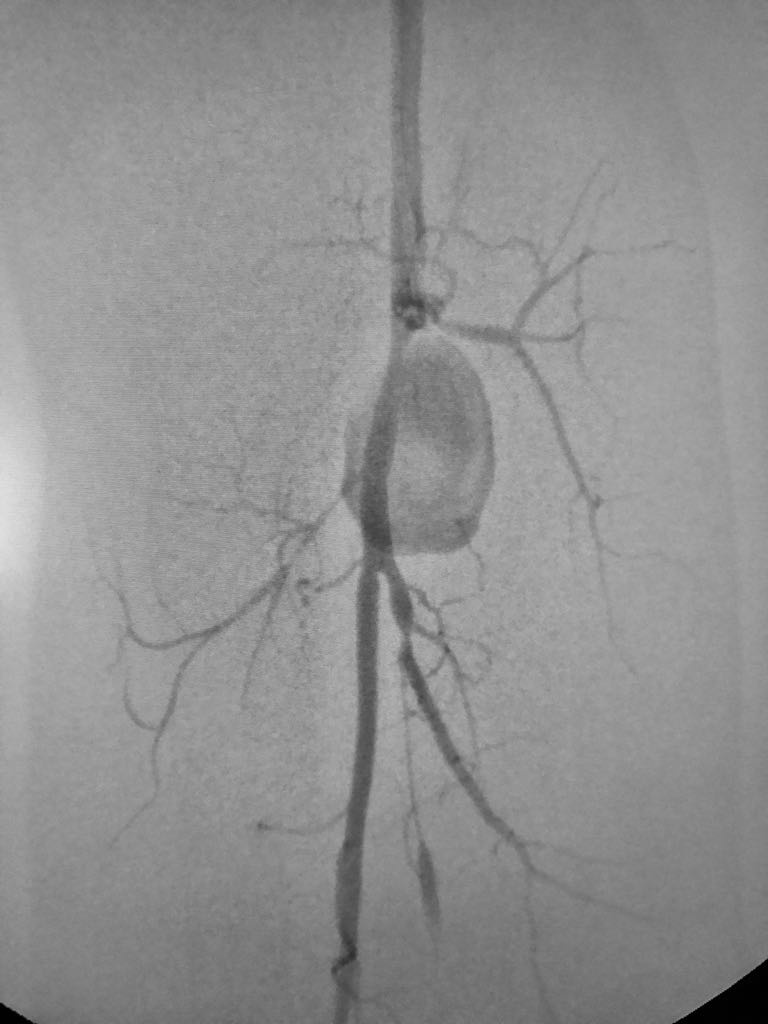

Somos una empresa enfocada en la atención en salud humana por medio del uso imágenes para ver diagnosticos y tratamientos de las diversas patologías con el uso de técnicas mínimamente invasivas en el territorio colombiano en el sector público y privado en búsqueda de una atención oportuna y de calidad a cada uno de nuestros pacientes.